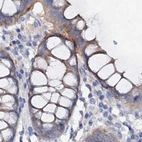

Immunohistochemical staining of human cerebral cortex, colon, duodenum and liver using Anti-ACY3 antibody HPA039219 (A) shows similar protein distribution across tissues to independent antibody HPA048187 (B).